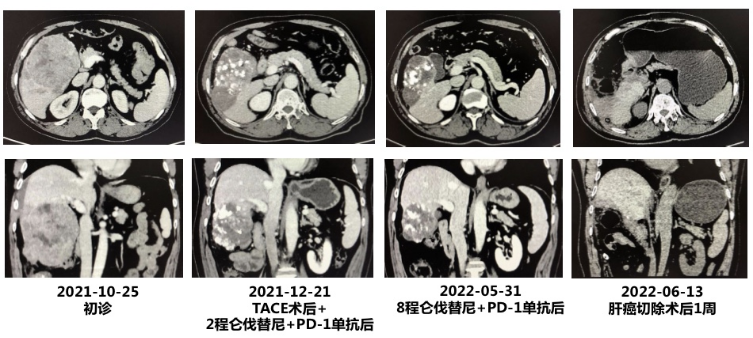

(2)CT影像的变化:

(3)手术后病理结果:(右肝)镜下示大片坏死,仅见极少残余肿瘤成分(<1%),周边肝组织形态尚规则,符合治疗后改变;另见淋巴结1枚,呈反应性增生(0/1)。

该患者初始诊断为CNLC Ⅲa期,因肝癌破裂出血就诊,急诊给予TACE栓塞止血。后经全身系统治疗(仑伐替尼联合PD-1单抗)治疗8周期,同时行抗乙肝病毒治疗后,AFP从90906 ng/ml降至正常;CT复查也提示为大PR,门脉右侧分支癌栓消失,最终创造了根治性切除的手术机会。术后病理结果也提示疗效非常好:MPR(残余肿瘤成分<1%)。

值得一提的是,尽管该患者初诊肿瘤巨大(超过10 cm),且伴肝癌破裂出血,但经过TACE栓塞止血后,创造了全身治疗的机会,并最终可能使得该患者长期生存。因此,即使对于分期较晚的肝癌初治患者,仍应创造机会抗肿瘤治疗。